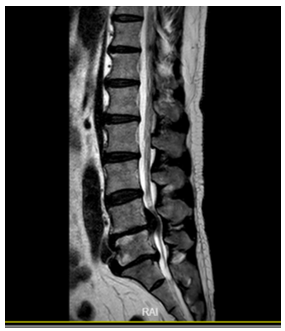

Before conducting the experiment, the collected dataset needed to be preprocessed. First, two experienced spinal surgeons used LabelMe Toolbox-master software to annotate the lesion areas in the abnormal group for the training and validation sets to later verify the algorithm's effectiveness; the normal group was not marked. The annotation process used the LabelMe Toolbox-master tool for standard naming, framing the sample's name, size, location, etc., with bounding boxes and annotating image prompt information. The markings and annotations were saved in XML file format. As shown in Table 3, this indicates the annotated location of the lesion area for edematous SCI signal changes.

Table 3. Labeling of lesion areas for edematous SCI

1 |

L4/5 significant disc herniation with free compression of the spinal cord, noticeable edema and high signal above the nucleus pressing on the spinal cord. |

||

|

2 |

Cervical spondylotic myelopathy, multi-segmental spinal canal stenosis, long-term compression of the spinal cord, MRI indicates local edema with high signal, significant behind the C5 vertebra. |

3 |

Cervical conus canal stenosis, C4/5, C5/6 disc herniation, high signal edema behind the 4th cervical vertebra in the spinal cord. |

After processing 500 images from the test set through the trained network models, the models sequentially predict and output visualization images, as shown in Figure 9, which includes some visualization results of edematous and lumbar disc herniation. Each image contains bounding boxes around the target area, along with the corresponding classification name and predicted probability value. These appropriately sized bounding boxes and predicted probabilities directly reflect the credibility of the disease. In Figure 9 below, representing a subset of the prediction set results, the credibility of SCI signals and the corresponding bounding boxes can be clearly seen, showing the location of the SCI signals within the bounding boxes and their corresponding credibility. This presentation of visualization results allows for direct observation of the predictive effectiveness of the images.